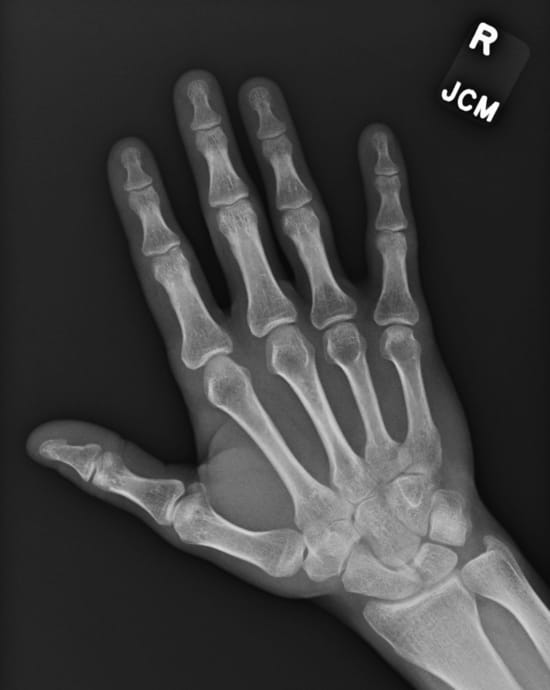

On Saturday, second to last day of the tour, I whacked my hand into a bannister on load-in and got the first two fingers pretty hard. I played that dance, unfortunately a double dance, with my first two fingers taped on my right hand:

When people asked how I was doing I enjoyed saying I was "about 80%" and bringing my taped hand into view.

I was worried I'd fractured them, but the next morning it turned out they were ok:

By that evening they were still not great, but I was able to play the last dance of the tour with all ten fingers! Which was much more fun.